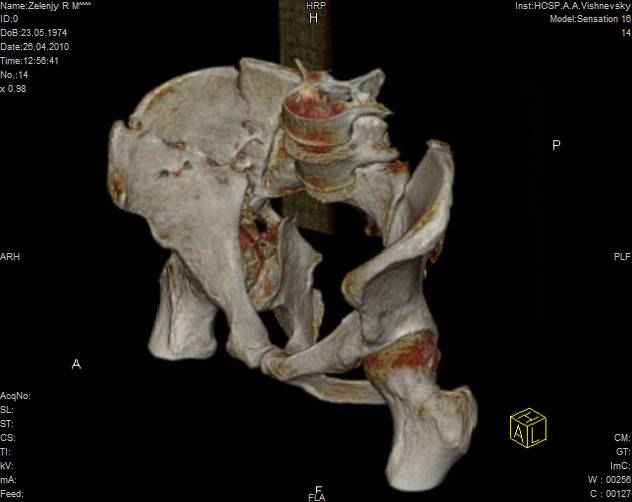

к таковым себя не причисляю, но...обычное дело для нашей страны - выкладывать 3D и не показывать стандартные проекции Judet. Дигност представляет те ракурсы, которые по-его мнению наиболее информативны, более того комп сам достраивает какие-то мелкие повреждения по 3D по своему усмотрению. По данной реконструкции можно предполагать высокий двухколонный перелом с оскольчатыми передней и задней колоннами, оскольчатую высокую переднюю колонну с задним полупоперечником или одно из перечисленных с вовлечение КПС. У меня впечатление за второй вариант, но нужно обследовать нормально - проекции, сканы.

высылаю дополнительно сканы.

Судя по представленным реконструкциям (не очень хорошего качества - много наводок)

мы имеем дело с полупоперечным переломом у которого отломался задний край или его отломали, превратив перелом в полный двухколонный.

По отдельным срезам и тем более по реконструкции трудно судить о сращении крыла и задней колонны с осевым скелетом.

Все выступающие коллеги высказались насчет необходимости стандартных снимков по Judet, потому что для определения тактики лечения переломов вертлужной впадины 3Д снимки малоинформативны.

Из того минимума, что представлено, мне кажется, мы имеем дело с двухколонным переломом вертлужной впадины. Обычно медиальный (центральный) "вывих" головки встречаются в сложных двухколонных переломах со смещением.